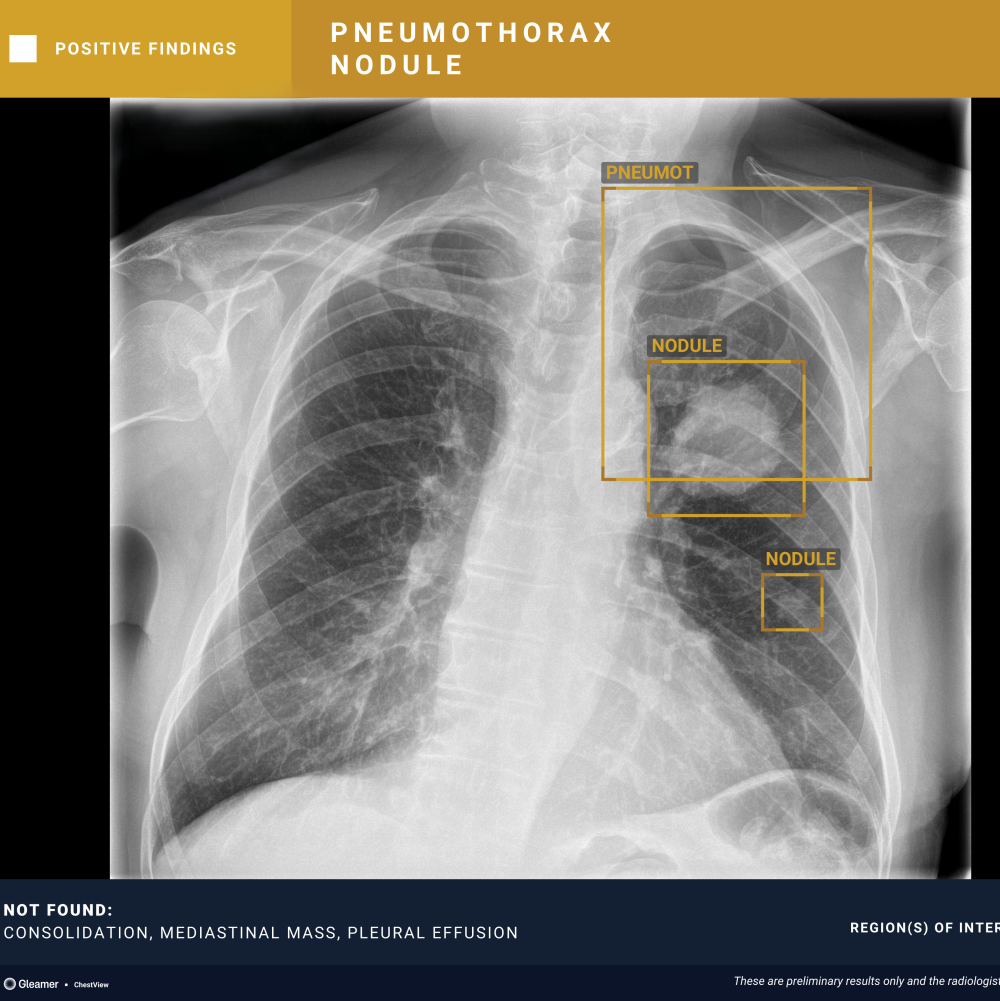

An 80-year-old male with a previously normal chest X-ray presents for CT evaluation 9 months later, which reveals findings suggestive of lung cancer.

ChestView detected the mediastinal mass on the initial X-ray.